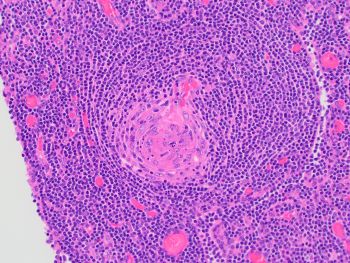

The lymph node is involved by Castleman disease, hyaline vascular variant. With disease localized to just the retroperitoneal “mass,” clinically the patient has unicentric Castleman disease. Histologically, the lymph node demonstrates a proliferation of follicles showing regressed/atretic hyalinized germinal centers with prominence of sometimes dysplastic-appearing follicular dendritic cells. There is radial penetration of germinal centers by blood vessels (so-called "lollipop" sign), and follicles with 2 or more germinal centers (so-called "twinning") are seen. There is broad expansion of mantle zones in an onion-skin appearance. The interfollicular areas contain increased thickened vessels with occasional sclerosis, occasional dysplastic-appearing follicular dendritic cells, and consists mostly of small lymphocytes with occasional transformed forms.